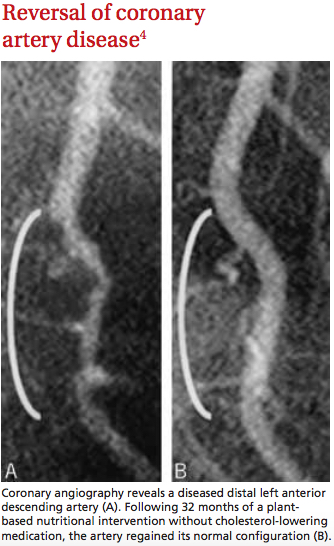

But his colleagues’ dubiousness didn’t last long. After placing patient after so-called-hopeless patient on his unique regimen, it became clear that Kempner’s diet worked. Really ridiculously well. And it became equally clear that the kidney wasn’t the only body part made happy by the new cuisine. Obesity, diabetes, high blood pressure, heart failure, coronary artery disease, psoriasis, and arthritis often saw major improvement or total reversal as a result of the diet. During the course of his career, Kempner treated over 18,000 patients with the above conditions—all by changing what went on the stabby end of their forks.